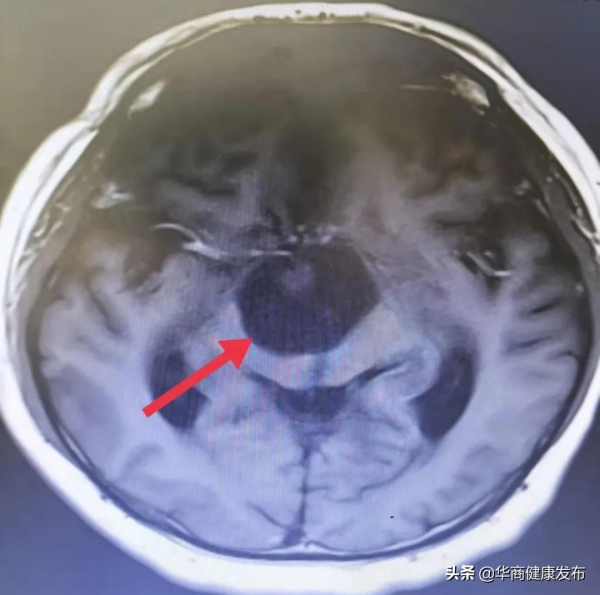

一月前,王大叔感覺四肢麻木且無力,家屬趕緊將他帶到醫院複查頭顱MRI,果然,結果提示是顱咽管瘤復發,且此次腫瘤體積比上次還要大一些,王大叔再次找到劉衛平教授,來到西安醫學院第一附屬醫院腦科醫院神外一病區就醫。

術中發現腫瘤位於垂體後上方,呈囊性改變,腦科醫院名譽院長劉衛平教授透過視交叉及垂體柄之間的間隙暴露腫瘤,充分保護好視交叉、垂體柄、大腦前動脈等周圍重要結構,吸出囊液,完整剝離囊壁,手術順利結束。